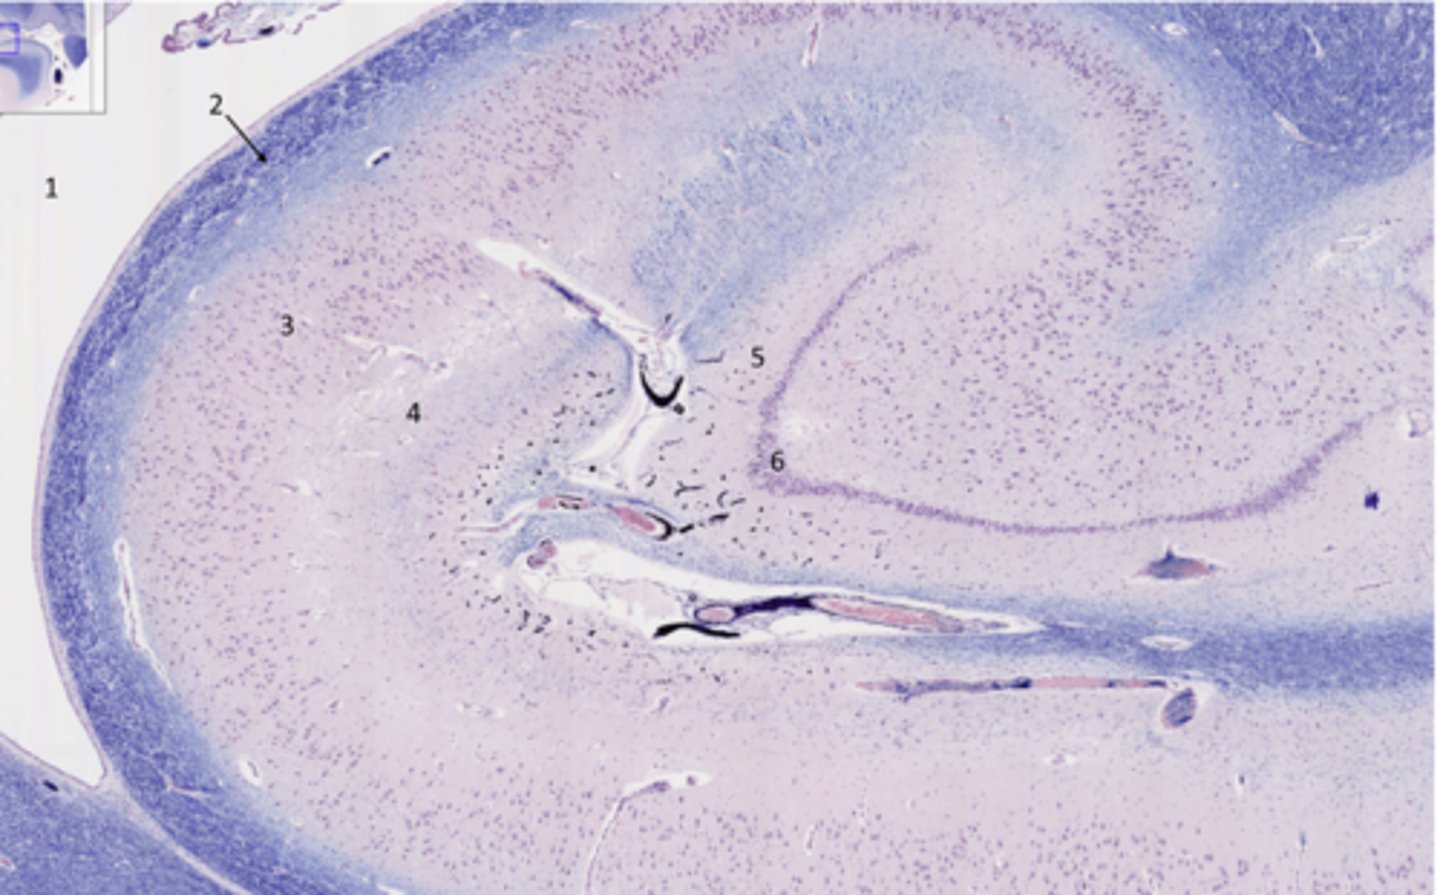

What part of the hippocampus is at 5 and 6

dentate gyrus

Identify the specific part of the brain in the inset

hippocampus